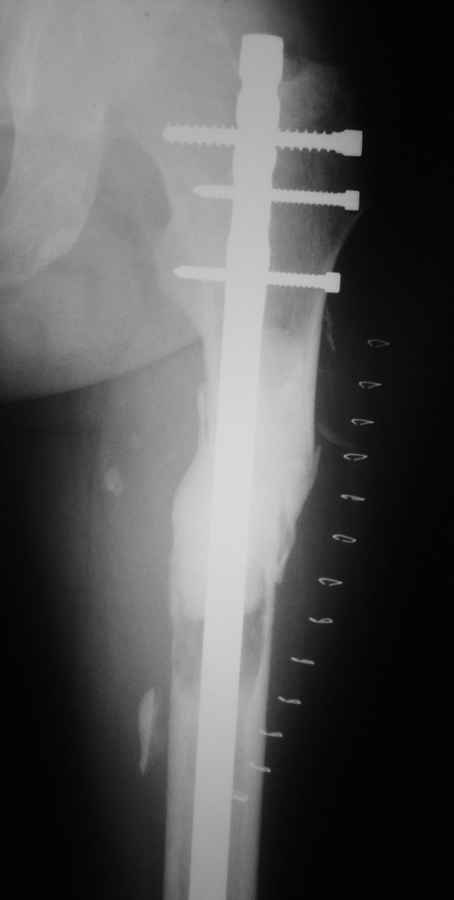

Провели резекцию костных отломков в общей сумме 5 см, частично резекция видимых и доступных участков опухоли, ОМС пластиной LCP DC винтами.

Извиняюсь за качество снимков, больного оперировали в другом районе, рентген-контроль вот такой предоставили. Прошло 10 дней, со стороны послеоперационной раны осложнений нет, анемия послеоперационная компенсирована.